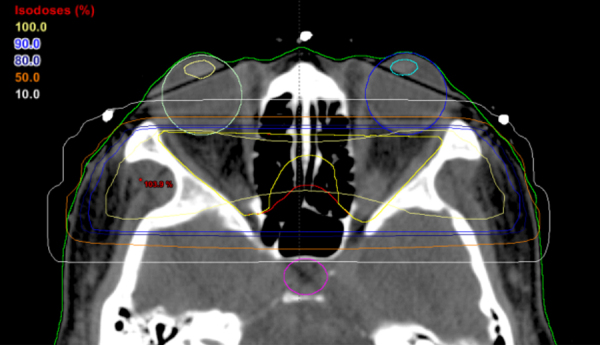

The patient's past medical history was significant for hypertension, hypothyroidism with Graves’ disease, a history of transient ischemic attacks (TIAs) and known lacunar infarctions. Radiation therapy had been performed for Graves’ opthalmopathy 14 years prior to presentation (see Fig. 3 for example of isodense lines in radiotherapy planning for TED). The patient had previously been investigated for the TIAs with a CT head non-contrast 4 years after her radiation therapy and no lesion was identified at that time.

Fig. 3.

Example radiation planning on axial computed tomography (CT) image for patient with TED demonstrating areas of irradiation from the 10% to the 100% isodose lines.